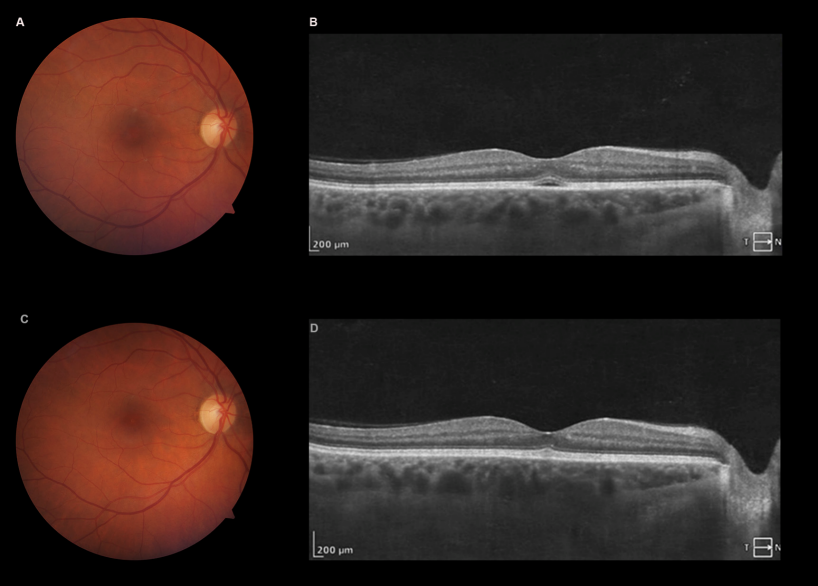

Figure 1: Fundoscopy the first evaluation, showing a discrete well-circumscribed, round yellow-orange lesion localized in the foveal region (foveolitis), retinal hemorrhages, macular oedema, soft exudates, and adjacent perivasculitis in OD (A). Right eye OCT (B) revealing an elevation and disruption of the foveal outer retina photoreceptors and/or retinal pigment epithelium, associated with cystic spaces in the inner retina, and accumulation of SRF. Left eye fundoscopy showing some discrete dot-blot retinal hemorrhages (C). OCT of the same eye was normal (D).

She returned 3 days later, referring improvement of her visual acuity (OD – 20/25). A new OCT was performed, showing improvement of the macular findings, with some residual SRF. CMT decreased to 246 µm. One week later, she had no complains, visual acuity in the right eye was 20/20. Fundoscopy and OCT were normal (Figure 2 [Fig. 2]).

Figure 2: Three days after initial visit, fundoscopy (A) showing improvement, and OCT revealing residual SRF (B). 10 days after first evaluation, fundoscopy (C), and OCT (D) were normal.